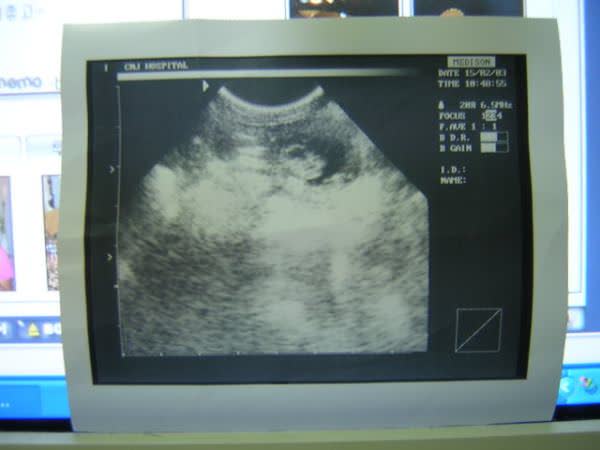

우리 극성쟁이 애기모습..

한시두 가만히 있질 않아요..